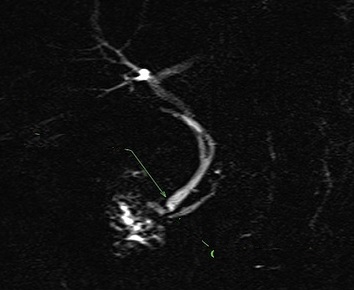

Image radiologique CPRM d'une pancreas

divisum de type I . Le canal pancreatique principale

est s'aboucher pans la papille mineur duodenum , le

canal ventral etre en jonction avec voie

biliaire principale et s'abouche au papille

majeur |

|

Image

radiologique CPRM d'une pancreas divisum de type II

. Le canal pancreatique principale est s'aboucher

pans la papille mineur duodenum . La voie biliaire

principale est s'aboucher au papille majeur duodenum

et le canal pancreatique ventral est totalement

absent |